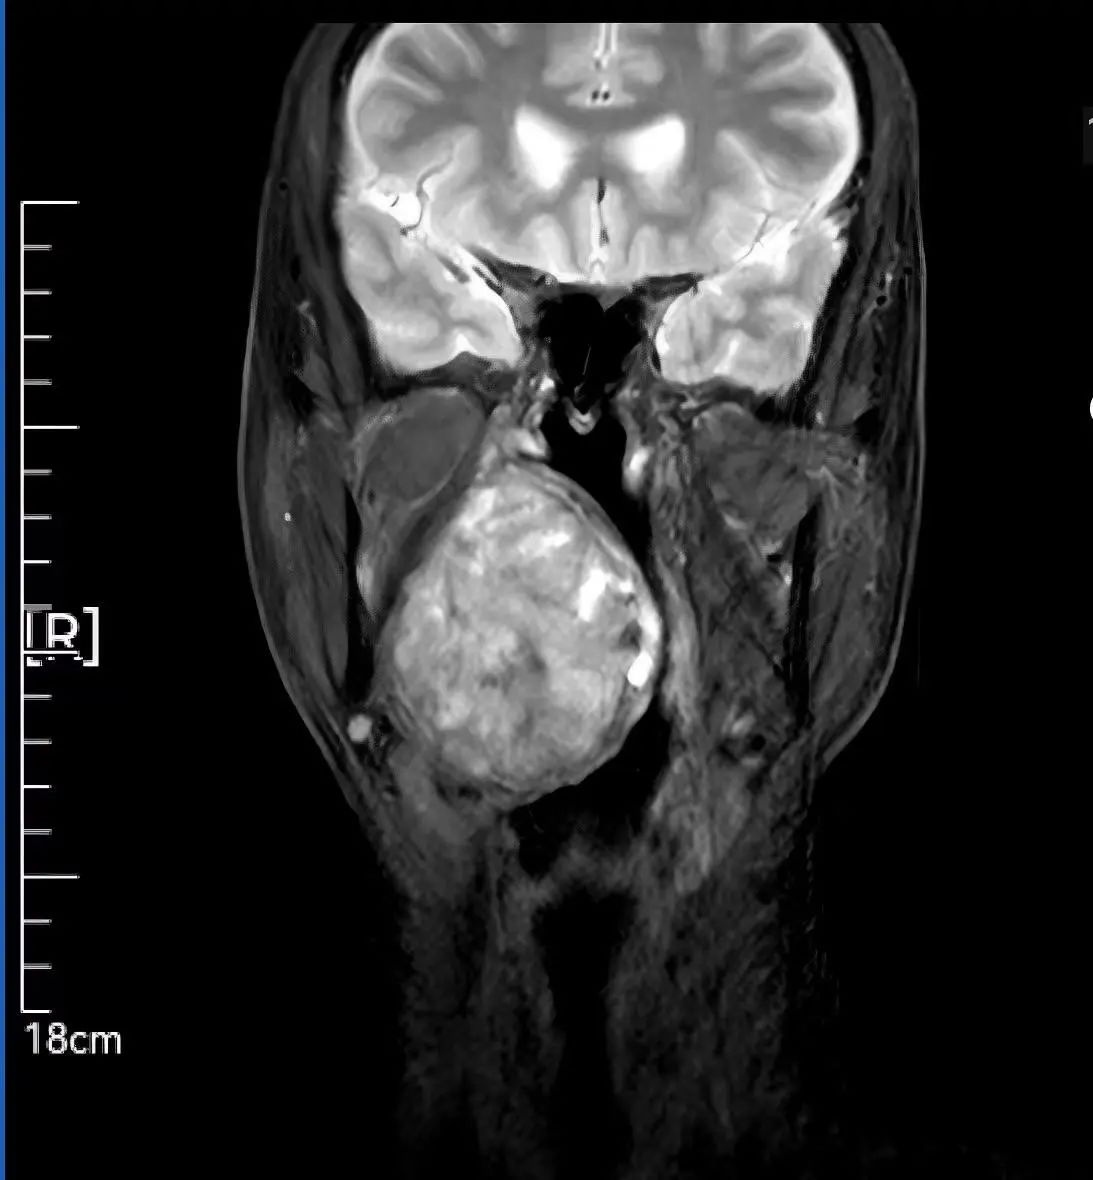

隱匿的“咽喉炸彈” 精準(zhǔn)診斷穿透病灶迷霧

59歲患者因腭部膨隆伴吞咽呼吸困難輾轉(zhuǎn)求醫(yī),最終就診于我院頭頸外科。李智林副主任查體發(fā)現(xiàn),患者咽部明顯膨隆,懸雍垂左偏,雙側(cè)扁桃體完全被腫瘤遮蔽,口咽腔嚴(yán)重狹窄移位。影像檢查顯示,6.2×1.4×7.3cm的腫瘤深居右側(cè)咽旁間隙,穿刺病理提示,明確為涎腺來(lái)源多形性腺瘤,毗鄰頸動(dòng)脈、顱底神經(jīng)群,手術(shù)風(fēng)險(xiǎn)極高。

顯微操作實(shí)施“咽喉拆彈” 三階段方案守護(hù)神經(jīng)功能 面對(duì)“手術(shù)禁區(qū)挑戰(zhàn)”,團(tuán)隊(duì)制定精細(xì)化方案: 術(shù)前攻堅(jiān):利用MRI精準(zhǔn)定位腫瘤邊界,制定血管神經(jīng)保護(hù)預(yù)案; 術(shù)中突破:先行氣管切開建立生命通道,經(jīng)下頜骨劈開入路顯微分離腫瘤,完整保留頸內(nèi)動(dòng)脈、面神經(jīng)等重要結(jié)構(gòu); 功能重建:以鈦板固定下頜骨,最大程度恢復(fù)咀嚼功能與面部形態(tài)。 歷經(jīng)數(shù)小時(shí)顯微操作,最終實(shí)現(xiàn)了腫瘤的根治性完整切除,并奇跡般地完整保住了患者的局部核心結(jié)構(gòu)和重要神經(jīng)功能。 可視化溝通破疑慮 從“被動(dòng)治療”到“主動(dòng)共信” 面對(duì)下頜骨劈開的手術(shù)方案,患者對(duì)創(chuàng)傷及并發(fā)癥充滿擔(dān)憂。李智林副主任創(chuàng)新采用“模型+預(yù)案”可視化溝通模式,直觀演示手術(shù)路徑,并針對(duì)患者對(duì)切口美觀的需求優(yōu)化入路設(shè)計(jì)。通過(guò)“治療方案共決策”機(jī)制,患者全程參與診療討論,最終從“被動(dòng)接受”轉(zhuǎn)為“主動(dòng)信任”。術(shù)后,在護(hù)士長(zhǎng)范改萍及病區(qū)護(hù)士長(zhǎng)李霞護(hù)理團(tuán)隊(duì)的精細(xì)照料下,患者恢復(fù)良好,吞咽和呼吸功能逐漸改善,目前已順利康復(fù)出院。 “是你們給了我第二次生命,頭頸外科團(tuán)隊(duì)用技術(shù)解除我的病痛,用真誠(chéng)治愈恐懼,這就是醫(yī)護(hù)最好的模樣?!边@段樸實(shí)的感言,成為“技術(shù)救治+人文關(guān)懷”的最佳注釋。 學(xué)科引領(lǐng)賦能精準(zhǔn)醫(yī)療 技術(shù)與溫度并重的診療范式 此次手術(shù)由頭頸外科主任李德志教授全程指導(dǎo),依托科室多學(xué)科協(xié)作(MDT)體系與顯微外科技術(shù)優(yōu)勢(shì),實(shí)現(xiàn)“精準(zhǔn)切除-功能保留-人文關(guān)懷”三重突破。未來(lái),團(tuán)隊(duì)將以更前沿的醫(yī)療技術(shù)、更溫暖的人文關(guān)懷,不斷攀登醫(yī)學(xué)高峰,守護(hù)區(qū)域內(nèi)百姓頭頸健康,為生命安全構(gòu)筑堅(jiān)實(shí)防線。